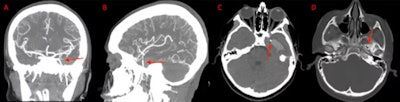

3. Orthodontic wire travels to boy’s brain, causing a seizure

(A) and (B) Coronal and sagittal view of the CT angiogram shows the wire penetrating through the skull floor of a 12-year-old boy. (C) Axial view of CT demonstrates the wire in the temporal lobe and the associated intraparenchymal hemorrhage. (D) Axial bone window CT shows the wire entering through the foramen ovale. Images courtesy of Morgan et al. Licensed by CC BY 4.0.

Imaging aided in the diagnosis of a 12-year-old boy in Texas who experienced a seizure after an orthodontic wire from his braces migrated into his temporal lobe.

After computed tomography (CT) scans and x-rays confirmed the metallic foreign object, which had traveled via the foramen ovale into the temporal lobe, as well as an associated intraparenchymal hemorrhage, the wire was removed without complications. The boy sustained no measurable damage to any structures within or around the foramen ovale, including the carotid artery, which would have been devastating, the authors wrote.